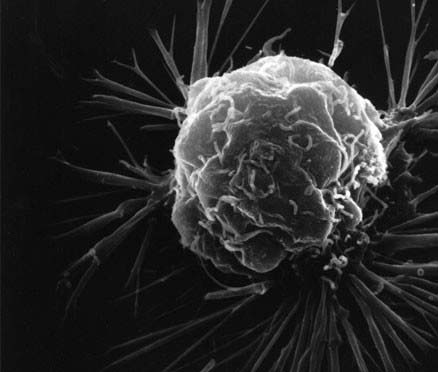

سلول های سرطانی سینه